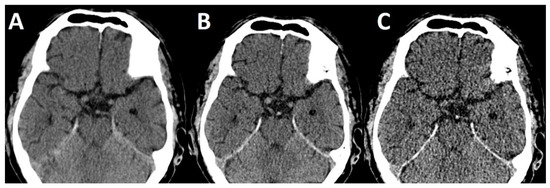

First, slice thickness on NECCT is pivotal when quantitative measurements of thrombus density are made [9]. In the literature, a wide range of slice thicknesses (0.625 mm [9], 1 mm [22], 2.5 mm [10], 3 mm [6], 4.8 mm [7] and 5 mm [20]) were employed. In this study, an increase of 1 mm slice thickness led to a decrease of approximately 4 HU in thrombus density. The decreasing rate of a hyperdense artery sign on thick slice reconstruction can be readily explained by the partial volume effect [9]. Especially short thrombi will be lost to blurring with surrounding cerebrospinal fluid when slice thickness exceeds thrombus dimensions (Figure 6). Kirchhoff and co-workers reported an additional influence of tube current with increasing thrombus density under increasing tube current [23] which could be the target for studies using dual-energy [12,24] or future spectral CT imaging studies.

Figure 6.

NECCT with 5 mm (A), 2.5 mm (B) and 0.625 mm (C) reconstructed slice thickness. Note the absence of a hyperdense basilar artery on 5 mm (A) slice thickness.